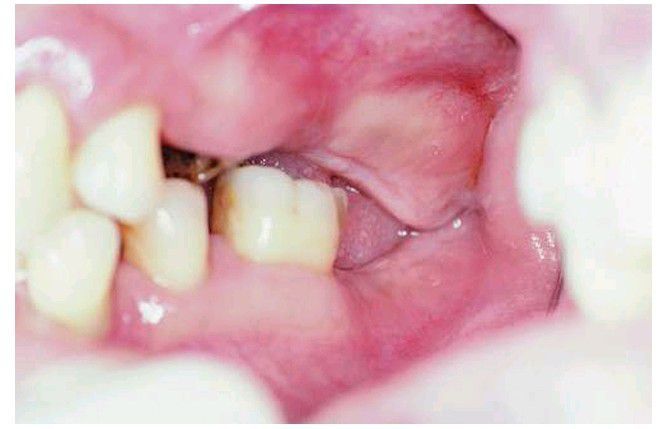

Examination of interarch relationships in proper vertical dimension often reveals lack of adequate space for prosthetic reconstruction. In this case, bony and fibrous tissue excess in the tuberosity area must be reduced to provide adequate space for partial denture construction.